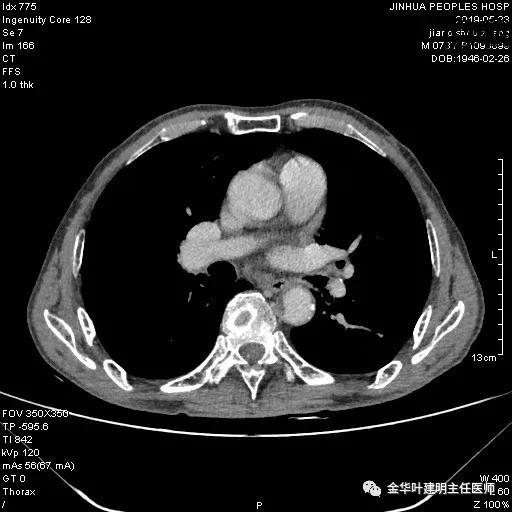

患者,男性,73岁,金华人。因“咳嗽咳痰伴胸闷2月,检查确诊左肺癌1周”入院。气管镜: 气管支气管内较多脓性分泌物,左肺上叶前段管腔新生物,局部活检、毛刷。气管镜病理:(左肺活检)鳞癌。阅胸部CT见左上叶开口处新生物,考虑需左上叶袖式切除及淋巴结清扫。具体CT表现如下:

考虑左侧大量胸腔积液,遂进一步胸部CT检查:

以上是肺窗表现,下面为纵隔窗影像: